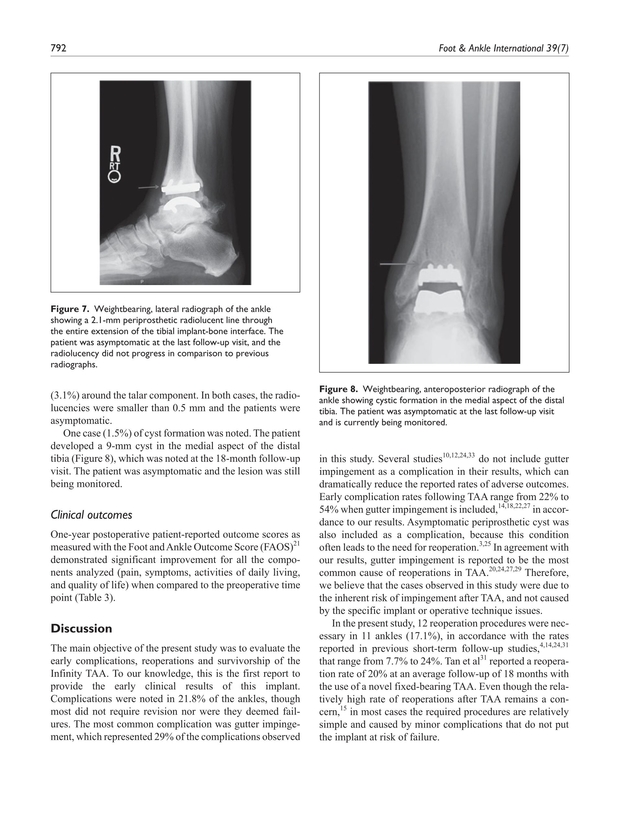

Ankle impingement can hurt along the medial gutter as well white circle. The incidence of gutter impingement was determined for patients with and without preemptive gutter resection at the time of implantation. The subsequent fibrosis and thickening of the injured posterior tibiotalar ligament and posteromedial capsule cause impingement between the medial wall of the talus and posterior margin of the medial malleolus resulting in formation of collagenous and fibrous meniscoid lesions and synovitis at the posteromedial ankle. Disturbing the cortex and periosteum with bone resection causes release of osteoblasts and mesenchymal stem cells initiating ossification 9 additionally oversizing the talar component can lead to gutter impingement 10.

If impingement should occur it typically arises an average of 17 months after total ankle replacement. Impingement after tar can be a source of pain and decreased patient satisfaction which in turn results in poor outcomes. Thus surgery is often pursued. Initially posteromedial symptoms do not predominate compared with the symptoms of the lateral ligament disruption and they usually resolve without specific treatment.

Medial gutter impingement was more common than lateral in our study but both were usually affected. X rays are often unremarkable but an mri or mr arthrogram may demonstrate the impingement. The functional outcome of 30 of the 34 patients who had subsequent gutter debridement was determined with 3 different outcome instruments. Rates of medial and or lateral gutter impingement after total ankle replacement are not insignificant.